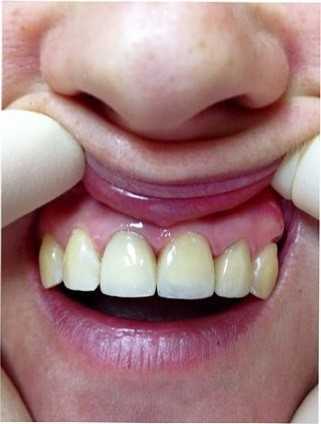

КАРАТ: работы специалистов (5)